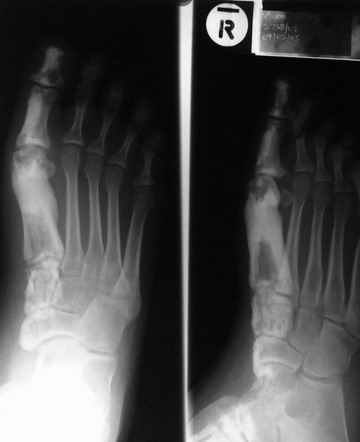

После меня выступал с новыми находками для своей коллекции Эмануэл Лакью Тесема, хирург-ортопед из Эфиопии: Мне понравились его находки:

Кто шустрый - при какой патологии встречается так называемые "суставы Шарко"?Второе приобретение доктора Эмануэла мне понравилось своим романтическим названием: Candle bone - <кость-в-виде-оплывающей-свечи> : Просто редкая патология:

VR>Второе приобретение доктора Эмануэла мне понравилось своим романтическим названием: Candle bone - <кость-в-виде-оплывающей-свечи> : Просто редкая патология: